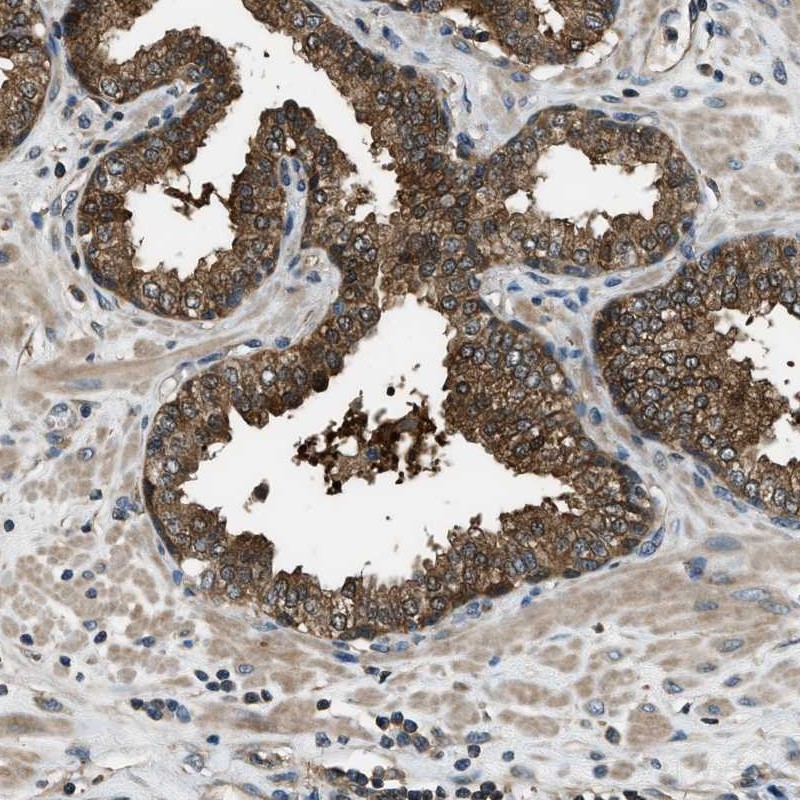

Immunohistochemical staining of human prostate shows strong cytoplasmic positivity in glandular cells.